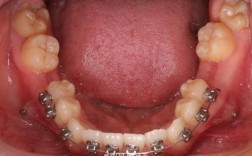

平面导板通常由树脂材料制成,呈平板状,戴于上颌或下颌牙齿的咬合面,仅与对颌前牙(或部分后牙)形成接触,而与对颌后牙无接触,这种设计打破了原有的咬合平衡,通过特定的力学刺激引发组织改建,具体作用如下:

深覆合是指上颌前牙牙冠覆盖下颌前牙牙冠超过1/3,严重时可能咬伤下颌牙龈,平面导板的作用图示中,可清晰看到导板与下颌前牙切端接触,而后牙区存在空隙,这种垂直分离使下颌前牙承受压低力,牙槽骨发生改建,牙冠向牙槽骨内移动;后牙脱离咬合接触,无咬合干扰的情况下,后牙牙槽骨受到牵引力,牙根向牙槽骨内生长,牙冠伸长,这一“前牙压低+后牙伸长”的双重作用,逐渐减小前牙覆盖,打开咬合间隙,改善深覆合。

在复杂病例中(如骨性深覆合、正畸-正颌联合治疗病例),平面导板可先通过非手术方式打开咬合、调整颌骨位置,为后续固定矫治器(如托槽)的粘贴、牙齿排齐及关闭间隙提供空间,提高矫治效率。